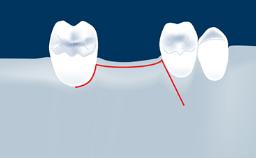

Sinus floor elevation using either the lateral window or transcrestal approach is a predictable surgical procedure with proven success, low complication rates, and high survival rates.

However, as with all surgical procedures, complications and failures do occur.

This learning module will provide an overview of the most commonly seen intraoperative and postoperative complications associated with sinus floor elevation and will discuss management in terms of preventative measures as well as treatment strategies.